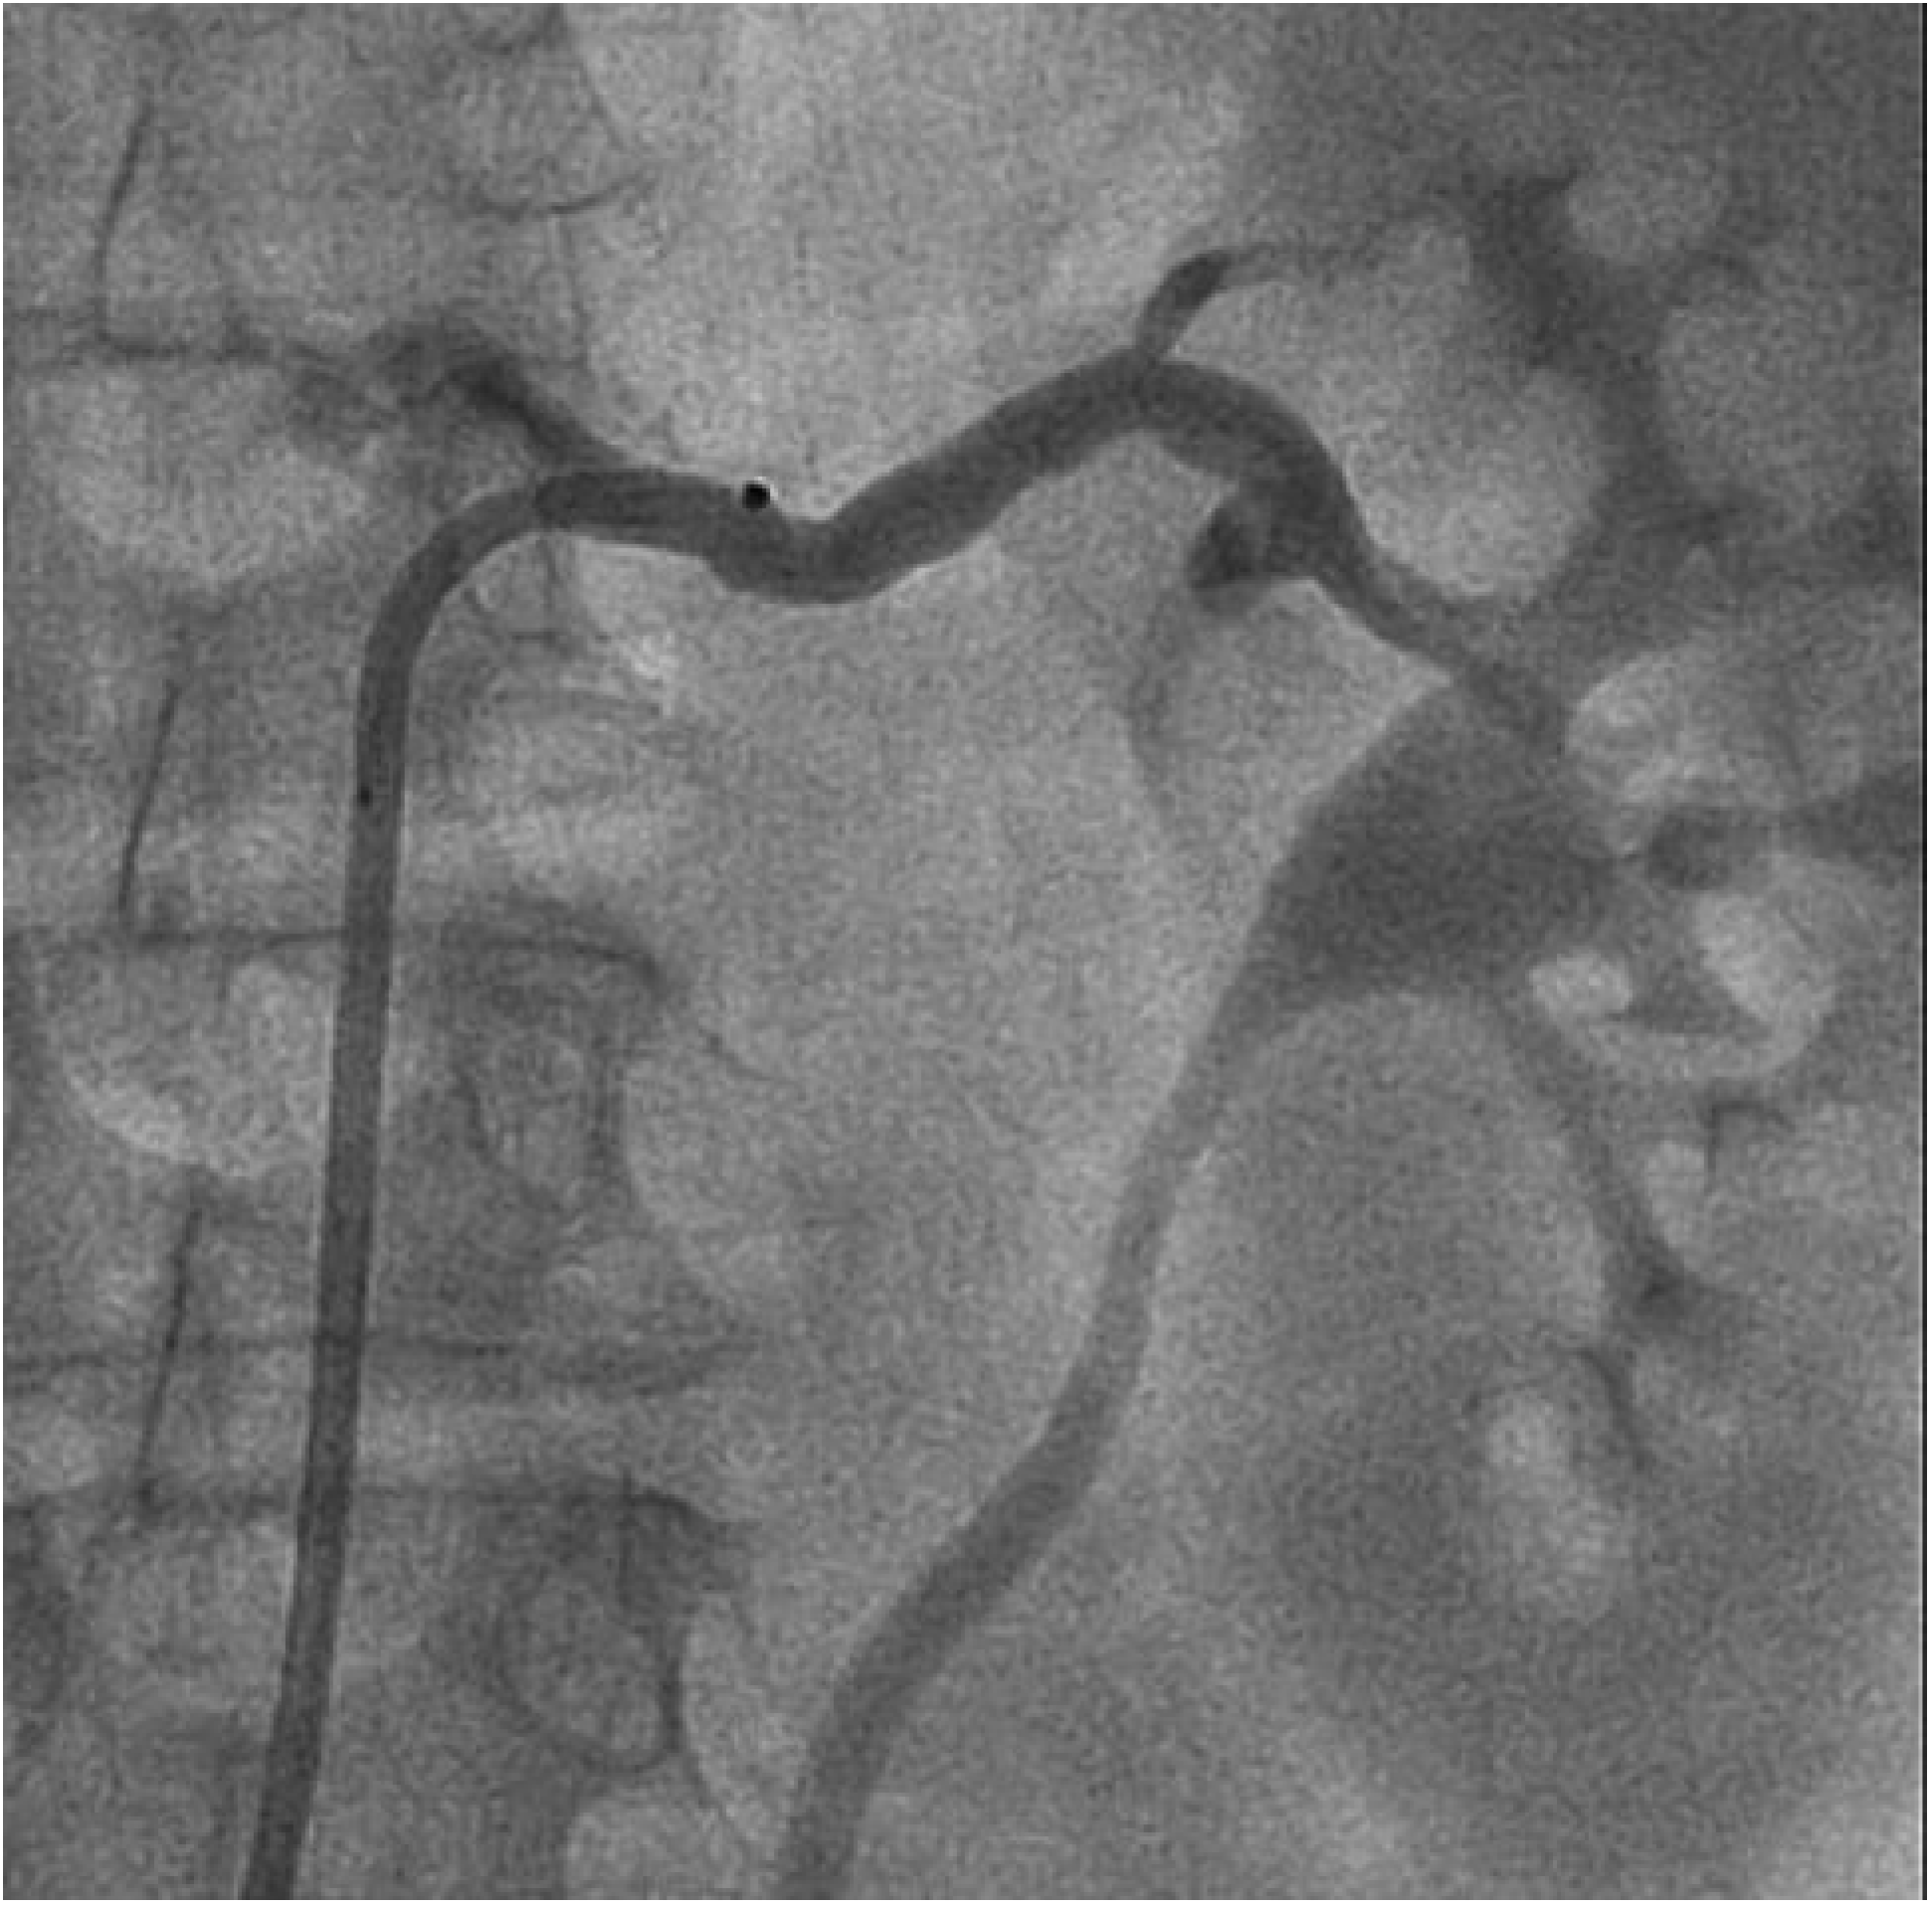

Abbildung 1.

Herz-MRT. A Darstellung des Herzen in der kurzen Achse: a = Wanddicke des Kammerseptums (normal <11 mm); b = Dicke der Lateralwand (normal <11 mm). B Vierkammerblick des Herzens.

Wir berichten über eine 66-jährige Patientin mit langjähriger therapieresistenter arterieller Hypertonie. Trotz antihypertensiver Therapie mit 5 Medikamenten konnten keine befriedigenden Blutdruckwerte erzielt werden. Subjektiv berichtete die Patientin von regelmässig wiederkehrenden Kopfschmerzen. Neurologische Abklärungen erbrachten keine eindeutige Ursache. Als Äquivalent eines hypertensiven Endorganschadens zeigte sich magnetresonanztomographisch eine linksventrikuläre Hypertrophie (Abb. 1). Die während der klinischen Verlaufskontrollen gemessenen Blutdruckwerte betrugen im Durchschnitt im Sitzen 175/88 mm Hg und im Stehen 169/86 mm Hg. Die initiale Langzeitblutdruckmessung zeigte Blutduckwerte im Tagesdurchschnitt von 154/77 mm Hg bei einer mittleren Herzfrequenz von 64 pro Minute (Abb. 2).